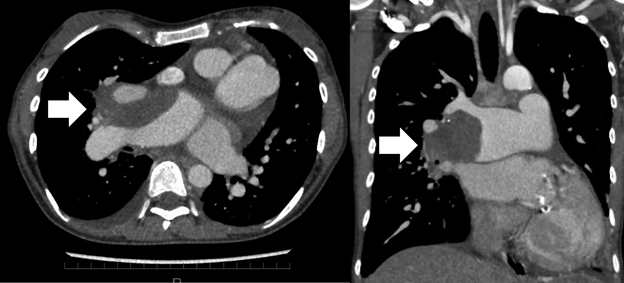

Fig. 2 CT scan images of pulmonary thrombus

Thrombus (white arrow) is recognized from the trunk of the right pulmonary artery to the middle lobe branch. The right lung S5 area is collapsed. Thrombus persisted after her symptoms improved.